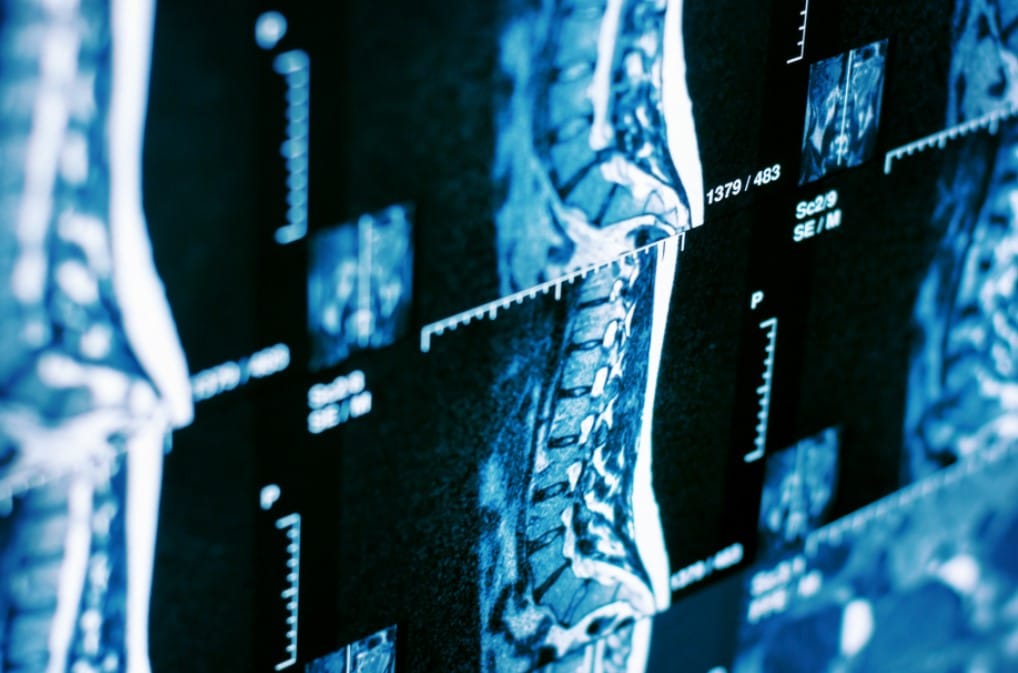

Escuchar la palabra “resonancia magnética” puede generar inquietud. Es totalmente normal. Muchas personas sienten ansiedad antes del examen, ya sea por el desconocimiento del procedimiento,

El dolor de espalda es una de las molestias más frecuentes entre los chilenos. Puede aparecer por malas posturas, caídas, sobreesfuerzo físico o simplemente por